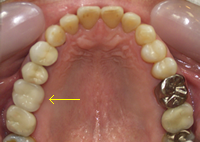

⑥ インプラント

| 治療前 | 治療後 |

主訴 |

歯のないところにインプラントを入れたい |

治療期間 |

4か月 |

治療費 |

インプラント¥200,000×1本 チタンアバットメント¥50,000×1本 メタルセラミックス¥100,000×1本 合計¥350,000(税別) |

治療内容について |

虫歯のために、すでに抜歯をされた患者様です。歯肉も骨も十分に治癒していましたので、歯周病の基本治療を行った上でインプラント手術を行いました。 両隣の歯は、虫歯のないきれいな歯でしたので、歯をたくさん削るブリッジではなく、インプラント治療を選択されました。歯は、治療したところからダメになることが多いので、このようなケースではインプラントの良さが最大限に発揮されます。 費用的にも、ブリッジでメタルセラミックスを入れると¥100,000×3本となり、あまり変わらなくなってしまいます。3本分のメンテナンスや破損のリスクも考える必要があります。治療法の選択に当たっては、やはり総合的に考えることが得策です。 |